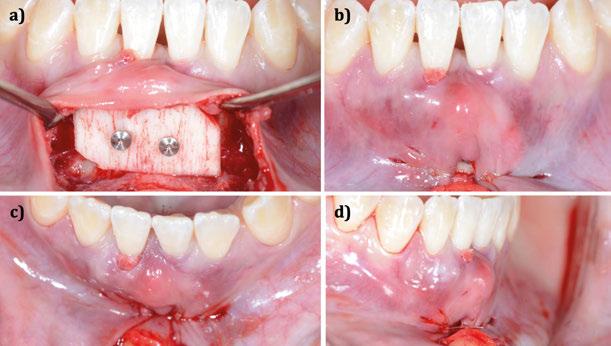

Figura 4. Intervención quirúrgica del caso clínico 1. a) posición del injerto suturado a través del colgajo de acceso apical vestibular; b) utilización de aloinjerto particulado (OraGRAFT® Aloinjerto Cortical Particulado MIX 70% Mineralizado / 30% Desmineralizado) para rellenar el interior del defecto y cubrir la dehiscencia ósea; c) cobertura de la dehiscencia ósea con el aloinjerto particulado; d) customización de la lámina de cortical acorde a las características del defecto (Lámina de cortical desmineralizada Cortiflex® Salugraft Dental).

Una vez preparado el lecho receptor, dada la existencia de una situación combinada de recesión gingival y una dehiscencia ósea vestibular con pérdida de inserción interproximal, se opta por la utilización combinada de un injerto de tejido conectivo autólogo tuberositario, un sustituto de origen alogénico (Lámina de cortical desmineralizada Cortiflex® Salugraft Dental) que se fija mediante dos chinchetas a ambos lados, cubriendo un injerto óseo de origen alogénico particulado (OraGRAFT® Aloinjerto Cortical Particulado MIX 70% Mineralizado / 30% Desmineralizado). Primero se suturó el injerto de tejido conectivo autólogo al colgajo, después se colocaron las partículas

de injerto óseo y, posteriormente, se fijó la lámina cortical.